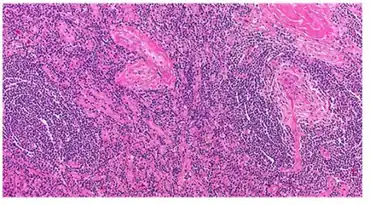

| Micrograph of lymph node biopsy demonstrating hyaline vascular features consistent with Castleman disease | |

The microscopic appearance (histology) of biopsied tissue from an enlarged lymph node must demonstrate a constellation of features consistent with Castleman disease. There are three patterns of characteristic histologic features associated with UCD:[5]

- Hyaline vascular - regressed germinal centers, follicular dendritic cell prominence or displasia, hypervascularity in interfollicular regions, sclerotic vessels, prominent mantle zones with an “onion-skin” appearance.

- Plasmacytic – increased number of follicles with large hyperplastic germinal centers and sheetlike plasmacytosis (increased number plasma cells).

- Mixed - features of both hyaline vascular and plasmacytic patterns

UCD most commonly demonstrates hyaline vascular features; however, plasmacytic features or a mixture of both hyaline vascular and plasmacytic features may also be seen in UCD lymph nodes.[4] The clinical utility of subtyping Castleman disease by histologic features is uncertain, as histologic subtypes do not consistently predict disease severity or treatment response.[5]